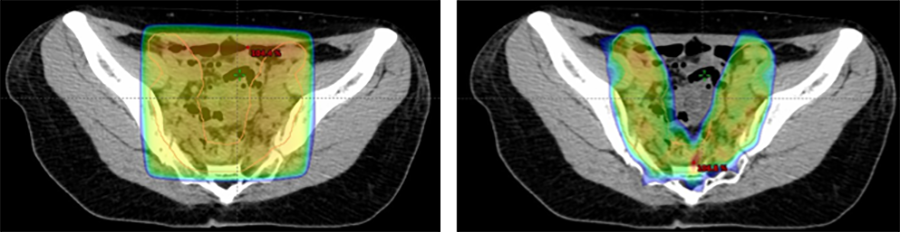

強度変調放射線治療:IMRT(Intensity-Modulated Radiation Therapy)

複雑な腫瘍形状に合わせて線量分布を形成する治療法です。腫瘍へ当たる放射線の線量を保ったまま、近接する正常臓器への線量を減らすことが出来るため、副作用に配慮した治療が可能です。様々な腫瘍に対して用いられますが、特に前立腺癌治療や頭頚部癌治療などにおいてはその有用性が広く知られています。